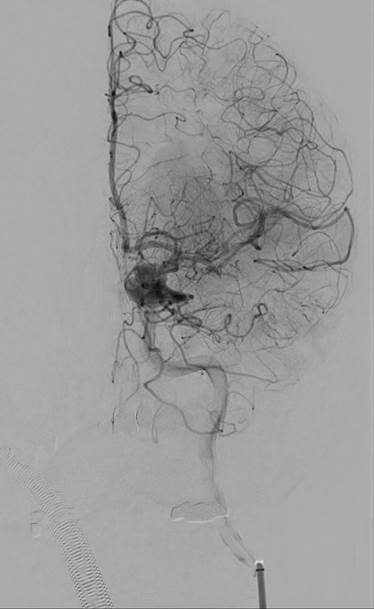

Ved hjerneinfarkt som skyldes blodpropp i en stor pulsåre i hjernen kan spesialiserte røntgenlegene fiske ut blodproppen ved trombektomi. Blodproppen blir fjernet mekanisk ved hjelp av et kateter som føres inn i pulsåren i lysken, opp gjennom hovedpulsåren og inn i hjernen.

Trombektomi (mekanisk fjerning av blodpropp).

Målet er å gjenopprette normal blodsirkulasjon og dermed begrense skade i hjernen. Jo tidligere det lykkes, desto mindre blir skadeomfanget og en oppnår bedre funksjonsnivå etter hjerneslaget.